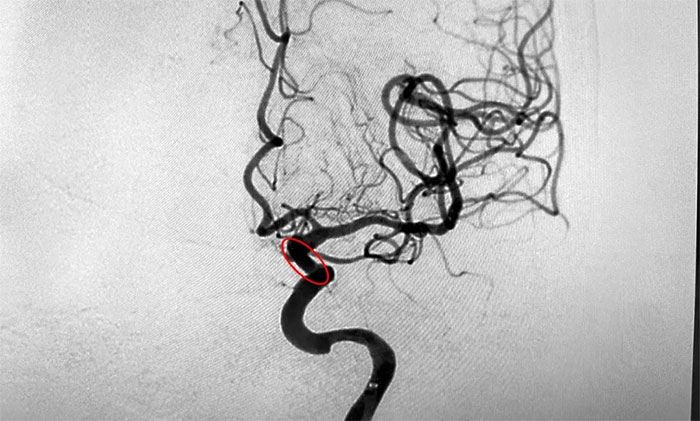

为进一步明确诊断并制定治疗方案,周君主任与医院学术副院长兼神经内科4A病区主任席刚明教授对患者病情开展了讨论评估,由席教授为患者进行DSA全脑血管造影检查,造影可见左颈内动脉岩骨水平段中度狭窄,左颈内动脉海绵窦段轻度狭窄,左颈内动脉眼动脉重度狭窄(狭窄程度约高于80%)。

▲ DSA检查影像